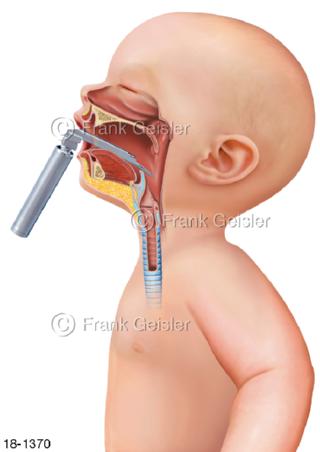

18-1370 Notfall Platzierung Laryngoskop Kleinkind Baby